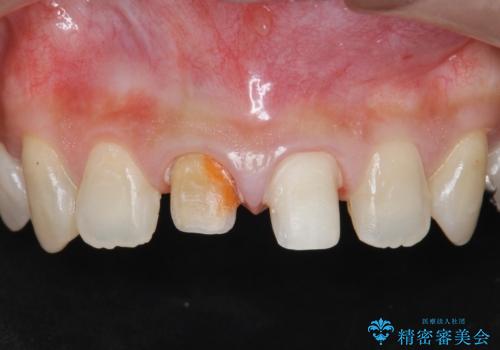

- 「 以前神経を取った歯の変色が気になる。前歯をきれいにして欲しい。」と治療を希望され来院されました。

目立つ上顎前歯に変色・大きな虫歯治療痕が見られ、審美障害を引き起こしています。